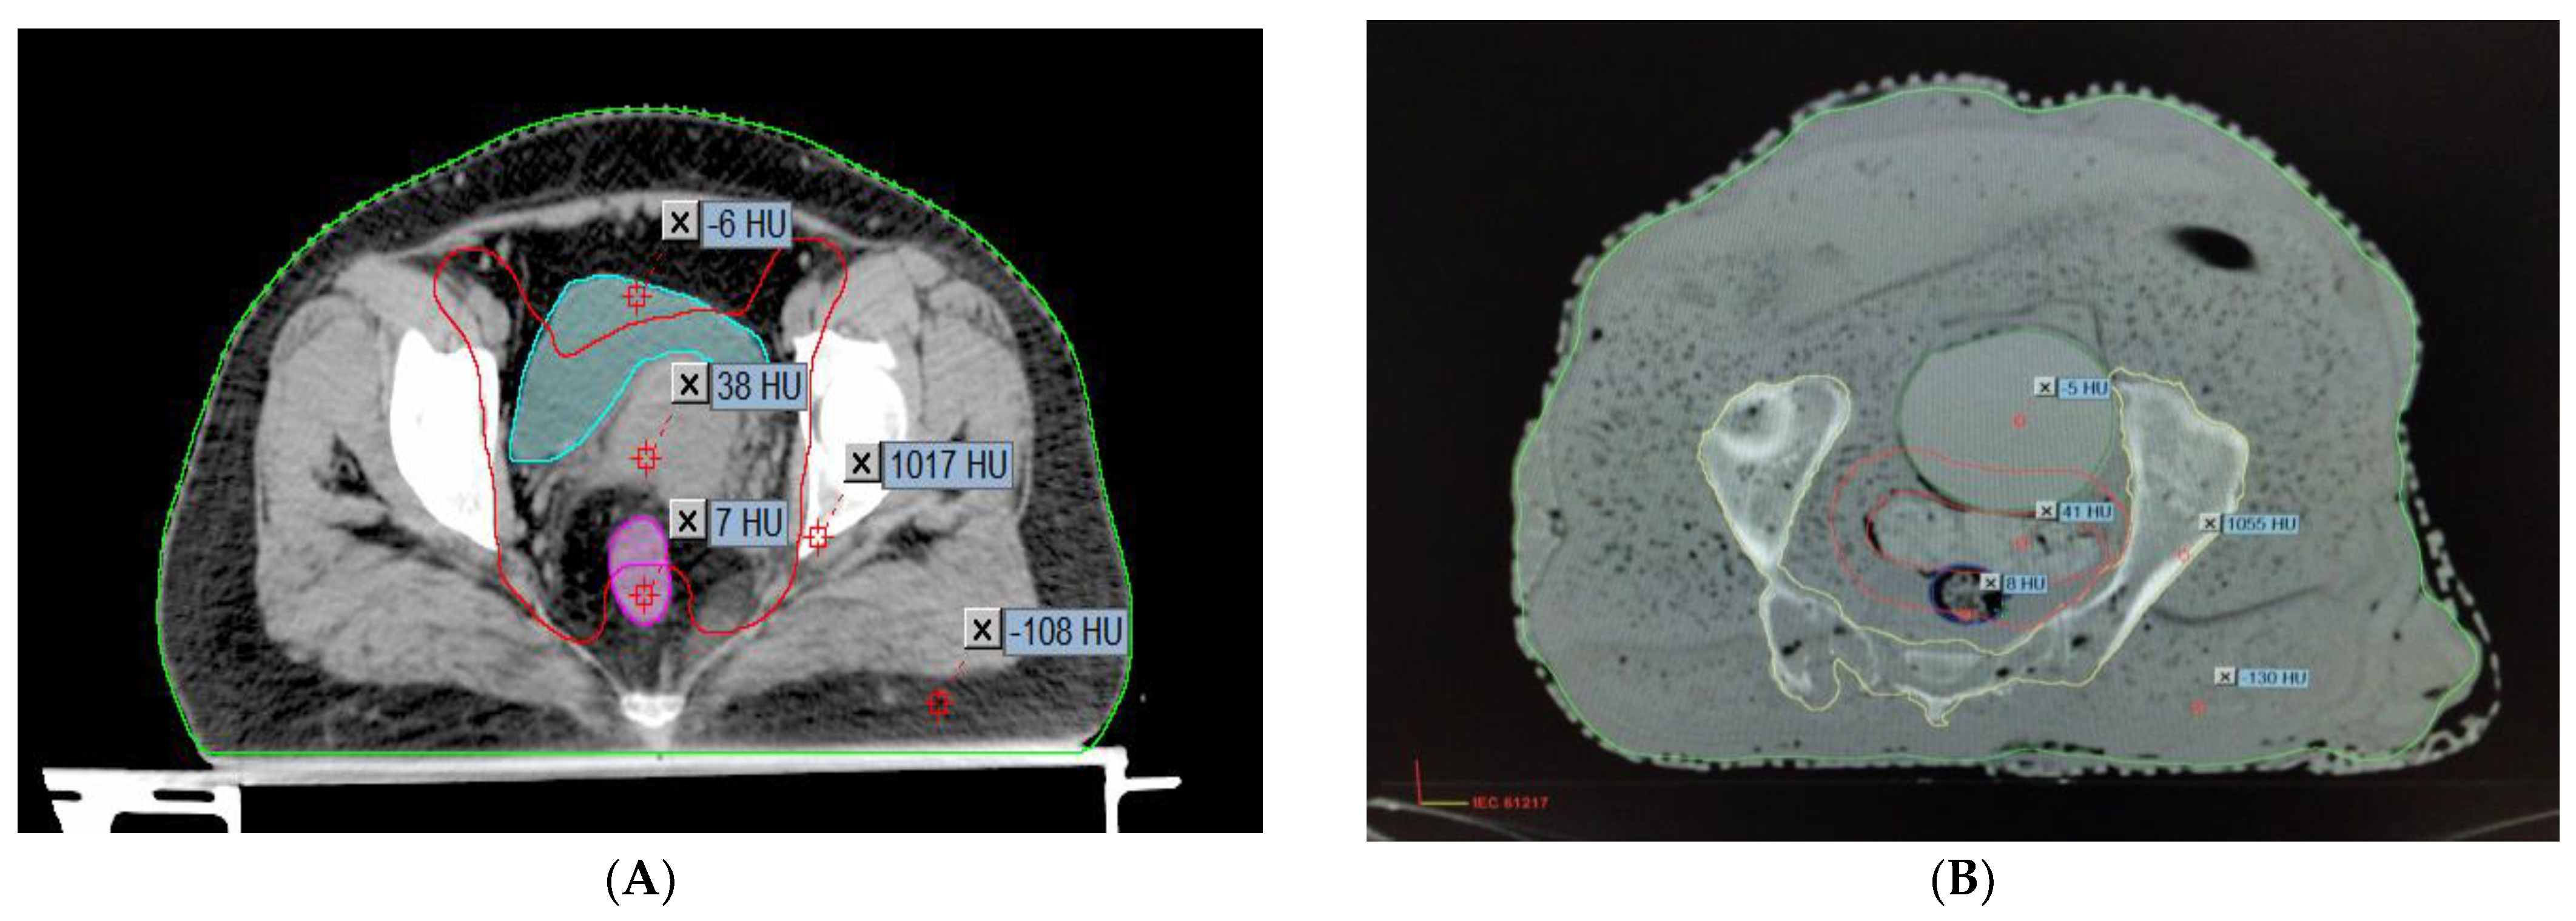

To determine how accurately the finished phantom product represents a real patient, the AHFP phantom was scanned with a CT scanner (Toshiba Alexion 16 multi-slice CT scanner) at 120 kVp and 250 mAs with a slice thickness of 2 mm. The CT images were transferred to the Eclipse treatment planning system (version 11.0.31) (Varian Medical Systems, Palo Alto, CA, USA). The CT images of the phantom were compared to CT images of randomly selected cervical cancer patients with similar scanning parameters (120 kVp, 250 mAs, and 2 mm slice thickness), which are shown in Figure 2A,B.

Figure 2.

HU value representation on CT images of (A) a real female patient and (B) the AHFP phantom.

Overall, there is good agreement between the measured CT number (HU) and relative electron density (RED) of the AHFP phantom and the patient groups. Table 2 displays the findings of the comparison between measured CT numbers from a sample of patients from our institution who were selected at random and the CT numbers of the phantom. Hence, it was observed that the AHFP fabricated for this study matched both the qualitative and quantitative aspects of the CT evaluation.

The results of our research, as presented in Table 2, demonstrate a close similarity between the Hounsfield unit (HU) and relative electron density (RED) values of the locally manufactured AHFP phantom and those of a human female pelvis. This finding aligns with previous research that emphasizes the importance of phantom design for dose measurement accuracy Johns & Cunningham [21]. Our study emphasizes the significance of tissue-equivalent phantoms, such as the AHFP, in achieving clinically relevant and precise dose measurements, as discussed by Almond et al. [22]. Numerous studies have contributed valuable data on the Hounsfield units and relative electron densities of human tissues, supporting the consistency and accuracy of these measurements. Winslow et al. [23] determined the Hounsfield units for human muscles, and established the soft tissue equivalent range as −55 to −155, with the bone tissue equivalent range being 660. This aligns with the research by Trujillo-Bastidas et al. [24] and Kanematsu [25], which reported relative electron densities for adipose, muscle, and bone tissues as 0.97, 1.05, and 1.4 and 0.96, 1.06, and 1.12, respectively. Similarly, the research conducted by Shrotriya et al. [26] and S. Singh et al. [27] revealed relative electron density values for bladder, rectum, fat, and bone tissues that closely align with our study’s findings (1.015, 1.069, 0.909, and 1.628, respectively). Shrotriya et al. (2018) reported relative electron densities of 1.31, 1.025, 0.91, and 1.6, respectively, while S. Singh et al. (2020) observed values of 1.04, 1.05, 0.89, and 1.63 for the same tissues. These consistent results across studies contribute to the overall understanding and validation of relative electron density values for different tissues, adding to the reliability of dosimetry calculations in radiation therapy planning.